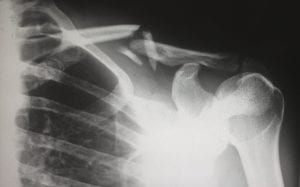

X-ray showing broken clavicle; image by Harlie Raethel, via unsplash.com.X-ray showing broken clavicle; image by Harlie Raethel, via unsplash.com.